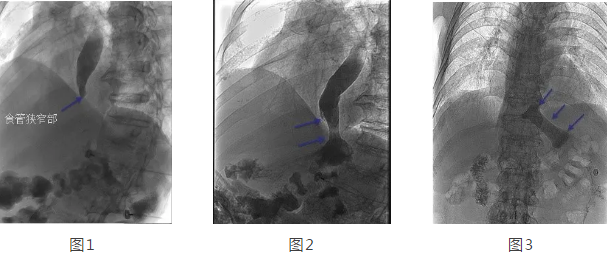

在韓國(guó)宏教授的帶領(lǐng)下,專家團(tuán)隊(duì)經(jīng)多方面評(píng)估后,決定在DSA下為劉大爺行食管造影 食管支架置入術(shù)。術(shù)中透視可見食管中上段擴(kuò)張明顯,食管下端賁門口明顯狹窄,造影劑淤積,呈線性緩慢進(jìn)入胃腔(見圖1),經(jīng)過準(zhǔn)確定位后,釋放食管支架,再次造影可見造影劑經(jīng)支架順利進(jìn)入胃腔(見圖2)。2天后再次造影見食管支架完全打開,位置正常,造影劑可順利通過支架(見圖3)。